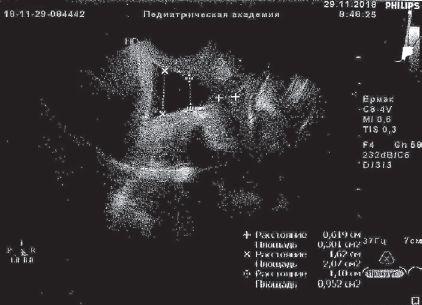

В анализах: общий белок крови 59 г/л, СОЭ 34 мм/ч, лейкоцитарный индекс интоксикации (ЛИИ) 2,6 усл. ед. (норма до 1,5), лейкоцитурия до 10 в поле зрения. Остальные анализы в норме. По данным УЗИ предполагаемая масса тела (МТ) плода 1403 г, плацента по передней стенке матки, 1-й степени зрелости, амниотический индекс 123 мм, шейка матки укорочена до 11 мм, цервикальный канал воронкообразно расширен на всем протяжении до 11–19 мм, выполнен до наружного зева плодным пузырем. Данные кардиотокографии и допплер-исследования кровотока в маточно-плацентарном пространстве в норме.

Получала сохраняющую беременность терапию с подключением трех сеансов мембранного плазмафереза (МПА) с возвратом гепаринкриомодифицированной аутоплазмы (при двух МПА по 200 мл), 12 сеансов ФК ультрафиолетовыми (№ 6) и лазерными (№ 6) лучами, без осложнений. После курса лечения анализы крови нормализовались, по данным УЗИ картина улучшилась, появилась сохранная часть шейки матки 6 мм, вероятно, за счет снижения внутриматочного давления в каудальном направлении. Пролабирования плодного пузыря за пределы наружного зева не визуализировалось в зеркалах и при УЗИ (рис. 1, 2).

Рис. 1. Данные ультразвукового исследования пациентки Ч., 30 недель беременности, до курса эфферентной терапии

Fig. 1. Ultrasonic examination of patient Ch., 30 weeks of gestation, before efferent therapy